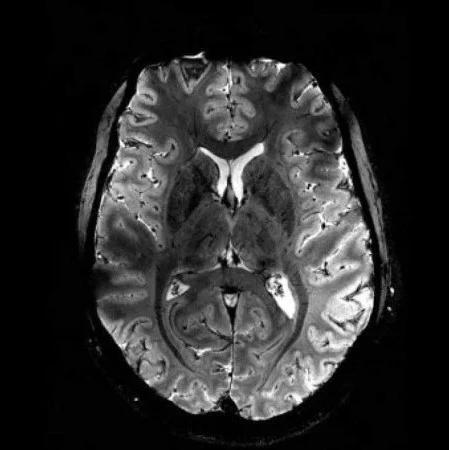

A plataforma BIP-Brain oferece análise quantitativa de imagens médicas para apoiar radiologistas e neurologistas no diagnóstico e acompanhamento de doenças neurodegenerativas, como o Alzheimer e a Esclerose Múltipla, e será continuamente aprimorada com base nas pesquisas realizadas pelo BIP-Group.